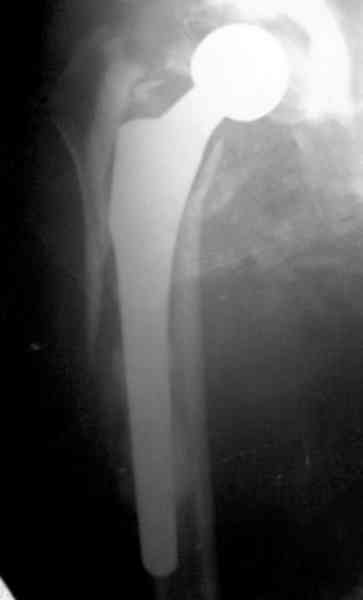

Представляю вашему вниманию снимки (прошу прошения за качество снимков) больной 48 лет с ревматоидным артритом, которой был сделан тотальный эндопротез справа,

контрольный снимок сделали только на 21день после операции (№1) и с интервалом 5 дней второй снимок (№2)

Судя по всему, произошел раскол наружной стенки бедра и ножка находится вне костного канала. В таком случае

решение одно - удаление ножки и установка новой в расчете на дистальную фиксацию. Конктреную модель подсказать тяжело из-за низкого качества Р-грамм.